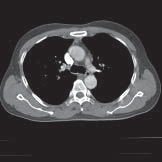

De CT-scanner (afgekort CT) is een apparaat dat door middel van röntgenstralen en een computer afbeeldingen maakt van uw organen, botten en weefsels. Zo’n afbeelding heet een CT-scan. Op een CT-scan is een dwarsdoorsnede van het te onderzoeken orgaan, bot of weefsel te zien. Hiervan kan op een computer achteraf een reconstructie worden gemaakt in een andere richting. Hieronder ziet u enkele voorbeelden van CT-scans.